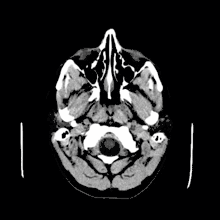

الكيسة الغروانية هي عبارة عن كيسة موجودة في الدماغ تحتوي على مادة جيلاتينية .تقع مباشرة خلف ثقبة مونرو في الجانب الأمامي من البطين الثالث حيث تنشأ من سقيفة البطين. نتيجة لمكان الكيسة فإنها من الممكن أن تسبب استسقاء الرأس الغير متصل وارتفاع في ضغط الدم داخل الدماغ. تمثل الكيسات الغروانية نسبة 0.5-1% من الأورام داخل القحف.[1]

من الممكن تشخيص الكيسات الغروانية من الأعراض الموجودة ولكنها ستتطلب اختبارات إضافية لأن أعراضها تتشابه مع تلك الخاصة بأمراض أخرى. التصوير بالرنين المغناطيسي والأشعة المقطعية يستخدمان لتأكيد التشخيص.[3]